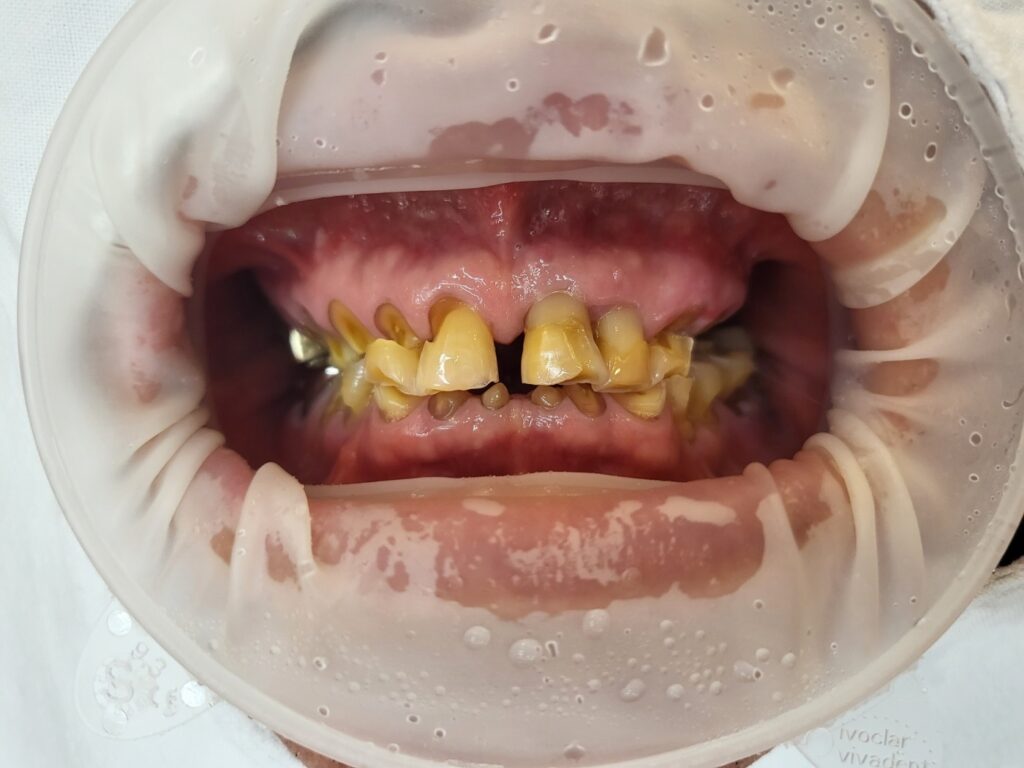

치아마모는 엑스레이로 쉽게 보이지 않을 수 있습니다. 전문가는 엑스레이만으로도 마모를 볼 수 있지만 일반인은 엑스레이로 구분이 어려울 수 있어요. 위에 올려진 입 안 사진을 참고해 주세요.

아래쪽 어금니 중에 자신의 치아머리 부분이 어느 정도 남아있는 치아들은 발치하지 않고 크라운으로 치료를 하게 됩니다. 치아머리가 거의 없는 치아들은 치아를 씌운다고 해도 자꾸 탈락, 즉 빠지게 되므로 발치한 후 임플란트로 치료하게 됩니다.